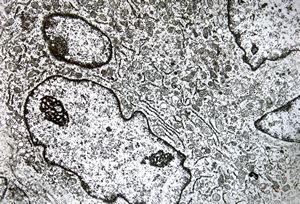

M,19y. | chondrocyte - chondrosarcoma - jaw